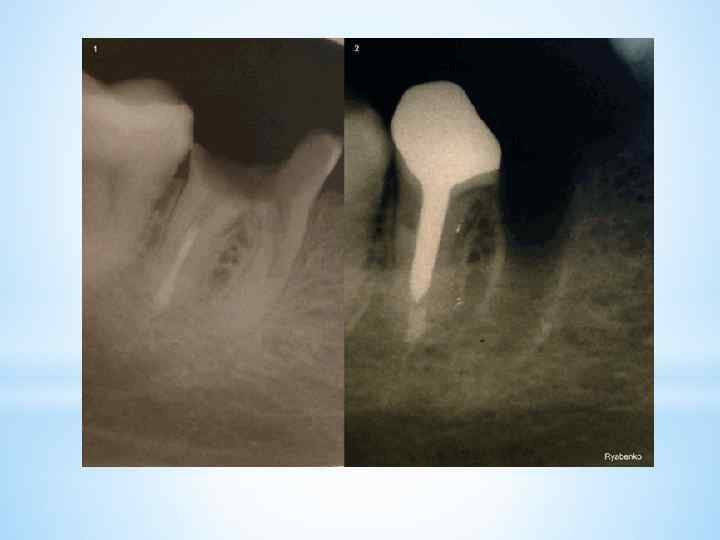

После проведения операции гемисекции, пациенту будет необходим рентгенологический контроль области вмешательства. *Так же Через 3 -4 месяца на рентгенограмме можно увидеть образование костной ткани на месте дефекта.

После проведения операции гемисекции, пациенту будет необходим рентгенологический контроль области вмешательства. *Так же Через 3 -4 месяца на рентгенограмме можно увидеть образование костной ткани на месте дефекта.